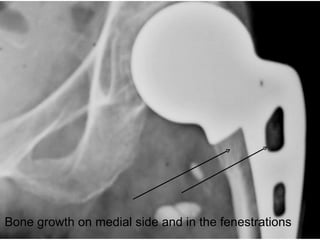

Bone growth on medial side and in the fenestrations

Bone growth onmedial side and in the fenestrations

Failure & Success - Amp? Most AMP fails on the table  Subsidence and Loosening depends on proximal fixation achieved on table Once the proximal locking holes filled with bone – the prosthesis is stable & long lasting. Hypertrophy of medial side, lateral wall hypertrophy, & new bone at the tip ensures long term success.

Proximal Fixation Tips & Tricks Impaction grafting: The most important area is the medial side near calcar. Graft should be inserted when nearly half of the prosthesis has gone inside. Fill the fenestrations of the prosthesis with bone grafts, as the prosthesis advances in to the canal. The color of the implant should not over-hang on the calcar. If done properly, it should rest on the neck and will compress the grafts.